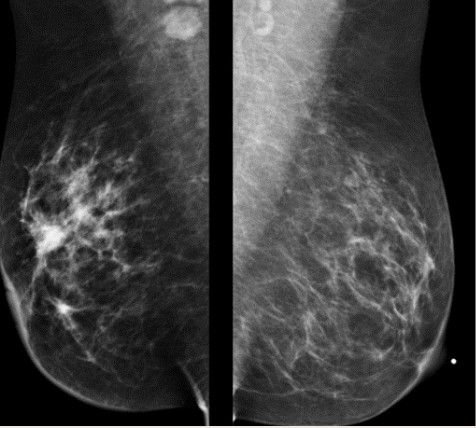

Figura 1. Mamografía: Nódulo hiperdenso, irregular, espiculado, con calcificaciones lineales finas de distribución segmentaria.